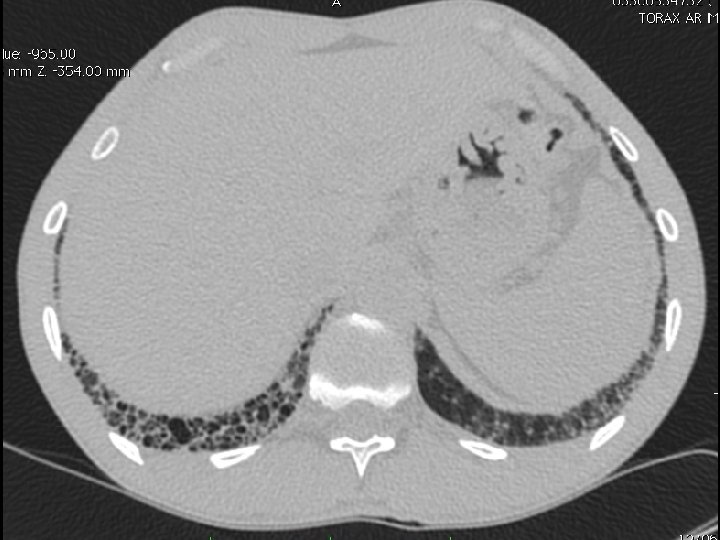

High-resolution CT scan

Subpleural, basal predominance Reticular abnormality Honeycombing with traction bronchiectasis UIPUIP Pattern

Subpleural, basal predominance Reticular abnormality Honeycombing with traction bronchiectasis Profuse micronodules UIPUIP Pattern Inconsistent with UIP Pattern